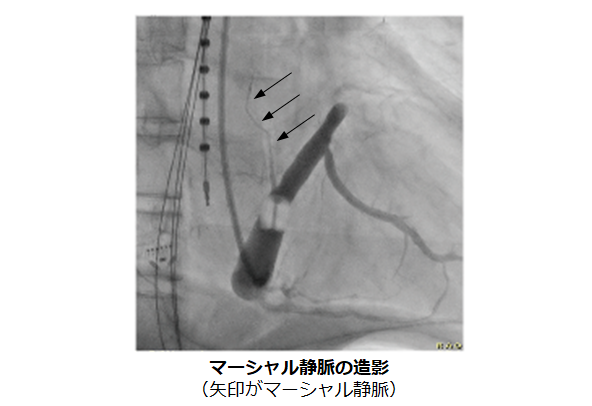

問題点として、心臓の筋肉が厚い僧帽弁輪においては高周波の焼灼だけだと効果が不十分な場合があります。不十分な焼灼は逆に他の不整脈(心房頻拍)の原因となってしまうことがありますので、それを解決するために当院では高濃度エタノールを併用してアブレーションを行います。

マーシャル静脈という僧帽弁輪付近にある細い血管に高濃度エタノールを注入することで心房を焼灼します。これを行うことで僧帽弁輪アブレーションの成功率が飛躍的に向上することが当院のデータでも示されています(※1)。エタノールによる焼灼は僧帽弁輪以外にも肺静脈や心臓周囲の自律神経をも焼灼すること、術後に心房頻拍が発症することも抑制する効果も示されており、心房細動アブレーションの成功率向上に寄与することが期待されています。